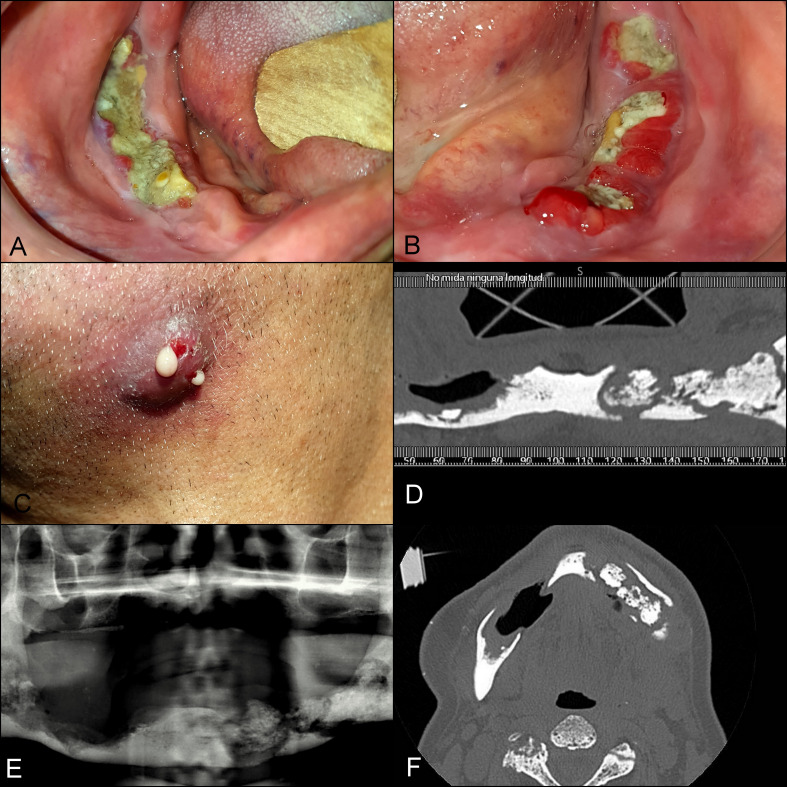

Abstract Image